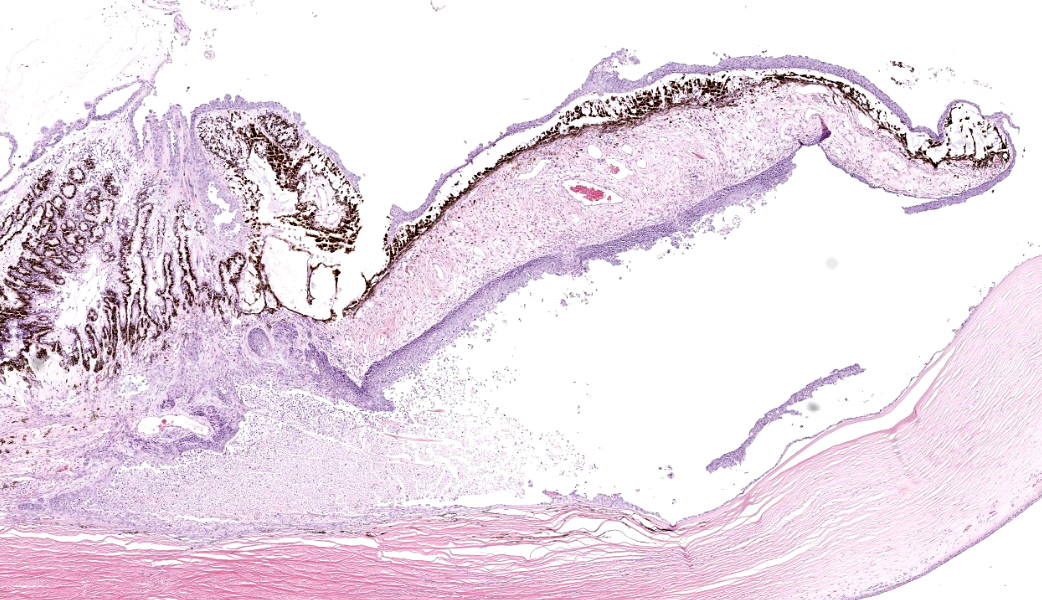

Eye: Overlying the corneal endothelium, anterior and posterior iris, portions of the lens epithelium, and the inner surface of the retina, as well as effacing and replacing the ciliary body, and occluding the drainage angle is an unencapsulated, densely cellular, infiltrative, neoplasm composed of epithelial cells arranged in broad dense cords on a moderate fibrovascular stroma. Neoplastic cells are polygonal with distinct cell borders, pronounced intercellular bridging, a moderate amount of pale eosinophilic cytoplasm, and irregularly round to vesiculate nuclei, with up to three distinct nucleoli. Anisocytosis and anisokaryosis is moderate. The mitotic rate is high with up to 12 mitotic figures per ten 40x HPF. Multifocally, neoplastic cells exhibit squamous differentiation. Near the optic nerve, the neoplastic cells invade the vascular and fibrous tunics, elevating and dissecting beneath the retinal pigment epithelium under a detached and coiled degenerate retina. At the caudal interior surface of the globe, there are numerous neutrophils admixed with abundant eosinophilic cellular and karyorrhectic debris and neoplastic cells infiltrate into the retinal vasculature.Contributor's Morphologic Diagnoses:

Secondary intraocular neoplasia. Aggressive malignancies of adjacent tissues may invade the eye and uvea through the cornea, sclera, or optic nerve.2 Scant descriptive literature is available; secondary neoplasia is most commonly encountered with squamous cell carcinoma of cow, horse, and cat, and nasal adenocarcinomas with orbital extension in dogs.2,4 A myxosarcoma involving the optic disc was most likely an extension from the orbit and optic nerve.2 Meningiomas of the optic nerve may extend through the lamina cribrosa into the globe.2 Other feline orbital neoplasms include zygomatic osteoma, parosteal osteoma, osteosarcoma, fibrosarcoma, undifferentiated sarcoma, and rhabdomyosarcoma.4

Conclusion. It is a common belief among specialists in veterinary and human ocular pathology that squamous cell carcinoma cannot originate from within the globe. (J.S. Estep, personal communication; December 26, 2019) Therefore, finding squamous cell carcinoma within the globe of a living patient should prompt the pathologist to warn clinicians to perform a thorough search for the primary neoplasm elsewhere.

This case contributor gives a thorough review of intraocular neoplasms in cats, touching on many major points of discussion during review of this case. Conference participants were readily able to reach a diagnosis of metastatic carcinoma, but not all were convinced that this was a metastatic squamous cell carcinoma (SCC) due to the lack of dyskeratosis within neoplastic epithelial cells, coupled with the lack of a primary mass found during workup. The prominent intercellular bridging between the neoplastic cells was noted by all, which can be a major feature of SCC; and squamous cell carcinomas are common tumors of the feline head; however other participants felt strongly that they could not rule out a carcinoma of other origin based on histology alone. For this reason, a morphologic diagnosis of “metastatic carcinoma” was ultimately favored by participants in this case due to the lack of clear-cut evidence of a squamous cell carcinoma on the H&E.There was no argument to be found on whether this was primary or metastatic, as the histologic evidence was strongly supportive of a metastatic process (i.e., the neoplasm primarily found within the highly vascular choroid and uvea, intravascular neoplastic cell emboli, etc.). The secondary changes in the eye were also discussed and it was concluded that this eye had glaucoma secondary to the neoplasm, evidenced by the retinal ganglion cell degeneration and loss with tapetal sparing, occlusion of the drainage angles by both the neoplasm and inflammation, buphthalmia (enlarged globe, attenuated and degenerative corneal epithelium, scleral thinning), and perivascular edema of the aqueous veins that drain the trabecular meshwork of the drainage angle.